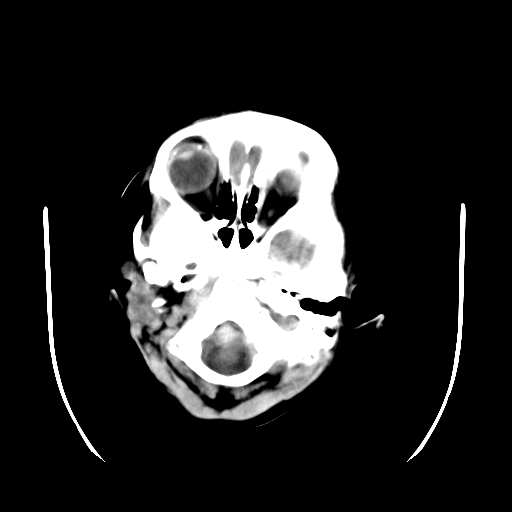

以下是引用深泽交通医院在2009-10-16 8:25:00的发言:[br]右眼环出血伴异物

以下是引用卜一在2009-10-16 15:01:00的发言:[br]右眼球挫裂伤伴异物!

以下是引用拾荒者在2009-10-17 18:38:00的发言:[br]鼻面部皮下积气,右侧睑缘及眼球壁高密度异物影,左侧眼球壁晶状体内侧缘处是圆形低密度影。低密度异物?应提请眼科医生注意。